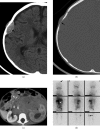

Neuroblastoma is one of the most common malignant neoplasms in childhood. The most common clinical presentation of this tumour is abdominal mass. However, affected children may have various clinical presentations as a result of disseminated metastatic disease or associated paraneoplastic syndromes at the time of diagnosis. In this article we have outlined the imaging findings in seven patients with "extra-abdominal" presentation of neuroblastoma and the pitfalls in making the correct diagnosis. The purpose of this pictorial review is to alert the general radiologist to the possible presentations of this common childhood malignancy to derive early detection and diagnosis.